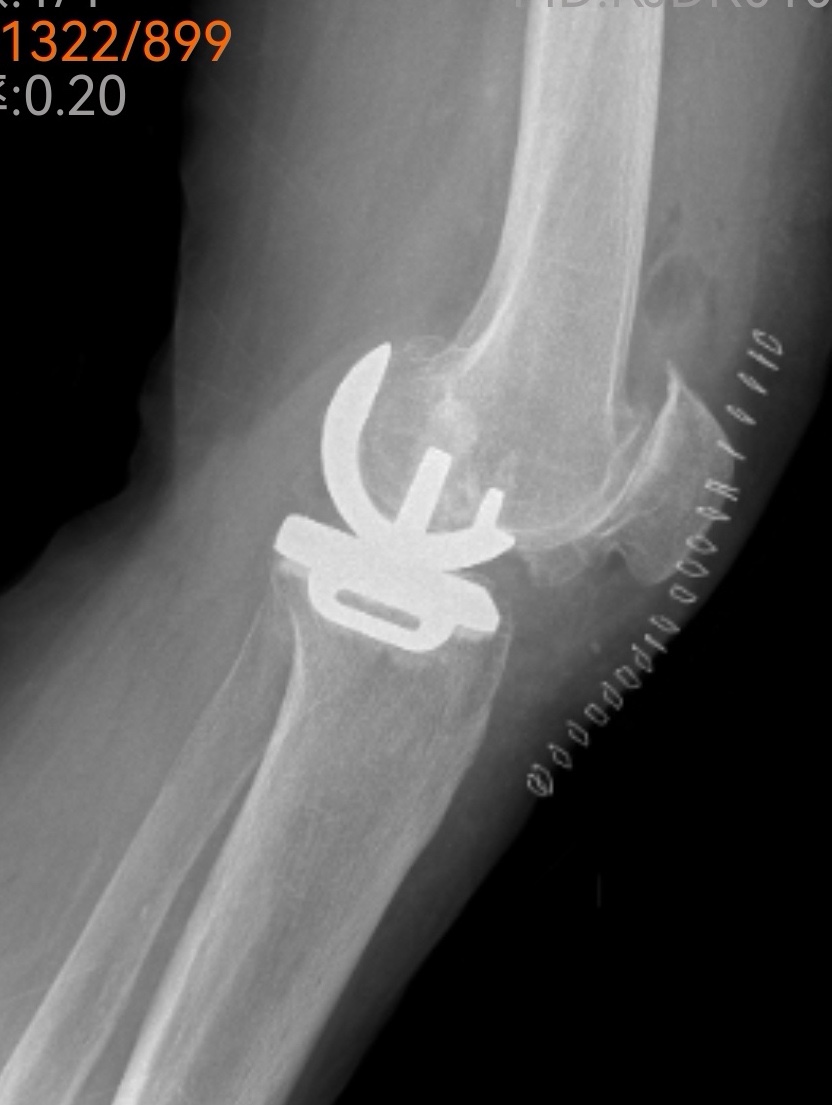

傳統(tǒng)的全膝關(guān)節(jié)置換固然能解決問題,但創(chuàng)傷較大、恢復(fù)期長。經(jīng)過團(tuán)隊(duì)綜合評估,魏海清主任提出了一個(gè)更精細(xì)的方案:“我們建議行左膝關(guān)節(jié)單髁置換術(shù)。這就像牙齒壞了,我們不必把所有牙齒都換掉,而是只替換損壞的部分。這種手術(shù)只替換磨損的軟骨和部分骨質(zhì),能最大限度保留健康組織。”他拿出膝關(guān)節(jié)模型,耐心地向一家人解釋手術(shù)原理:“您看,膝關(guān)節(jié)分為內(nèi)側(cè)、外側(cè)和髕股三個(gè)部分。您的磨損主要集中在內(nèi)側(cè),所以我們只需置換這一部分。”這種個(gè)體化、精準(zhǔn)化的治療理念,讓原本忐忑的一家人逐漸安心。

微創(chuàng)手術(shù),一小時(shí)改寫生活

手術(shù)室里,骨科、麻醉科、手術(shù)室團(tuán)隊(duì)配合默契。微創(chuàng)切口僅有傳統(tǒng)手術(shù)的一半大小,精細(xì)的操作在關(guān)節(jié)鏡輔助下進(jìn)行。沒有大刀闊斧的創(chuàng)傷,只有精準(zhǔn)細(xì)致的重建。一小時(shí)后,手術(shù)順利結(jié)束,出血量僅約100毫升。“這么快?”等候在外的兒子們幾乎不敢相信。魏海清主任走出手術(shù)室,微笑點(diǎn)頭:“很順利,單髁置換本來就是微創(chuàng)手術(shù),對患者損傷小。”

出院前,李阿姨特意換上了從家鄉(xiāng)帶來的紅色外套,與醫(yī)療團(tuán)隊(duì)合影留念。鏡頭前,她的笑容燦爛而真實(shí)。魏海清主任看著這位千里求醫(yī)的患者,心中感慨:“上了年紀(jì)的人最怕關(guān)節(jié)問題導(dǎo)致無法活動(dòng)。長期臥床會(huì)引起一系列并發(fā)癥,嚴(yán)重影響生活質(zhì)量。我們采用的改良微創(chuàng)手術(shù),出血少、損傷小、恢復(fù)快,符合快速康復(fù)理念。”他頓了頓,繼續(xù)說道:“患者跨越兩千多公里選擇我們,這份信任沉甸甸的。作為醫(yī)生,我們唯有以精湛技術(shù)和全心關(guān)懷相回報(bào),才不負(fù)這份生命的托付。”